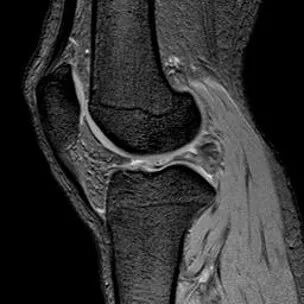

半月板水平撕裂

1、水平撕裂

2、较少见3、III级高信号与胫骨平台平行,到达半月板的游离缘或一侧关节面

(半月板水平撕裂)

半月板纵行撕裂

1、纵行撕裂2、撕裂方向和半月板长轴方向平行3、垂直或斜行的III级高信号

(半月板纵行撕裂)